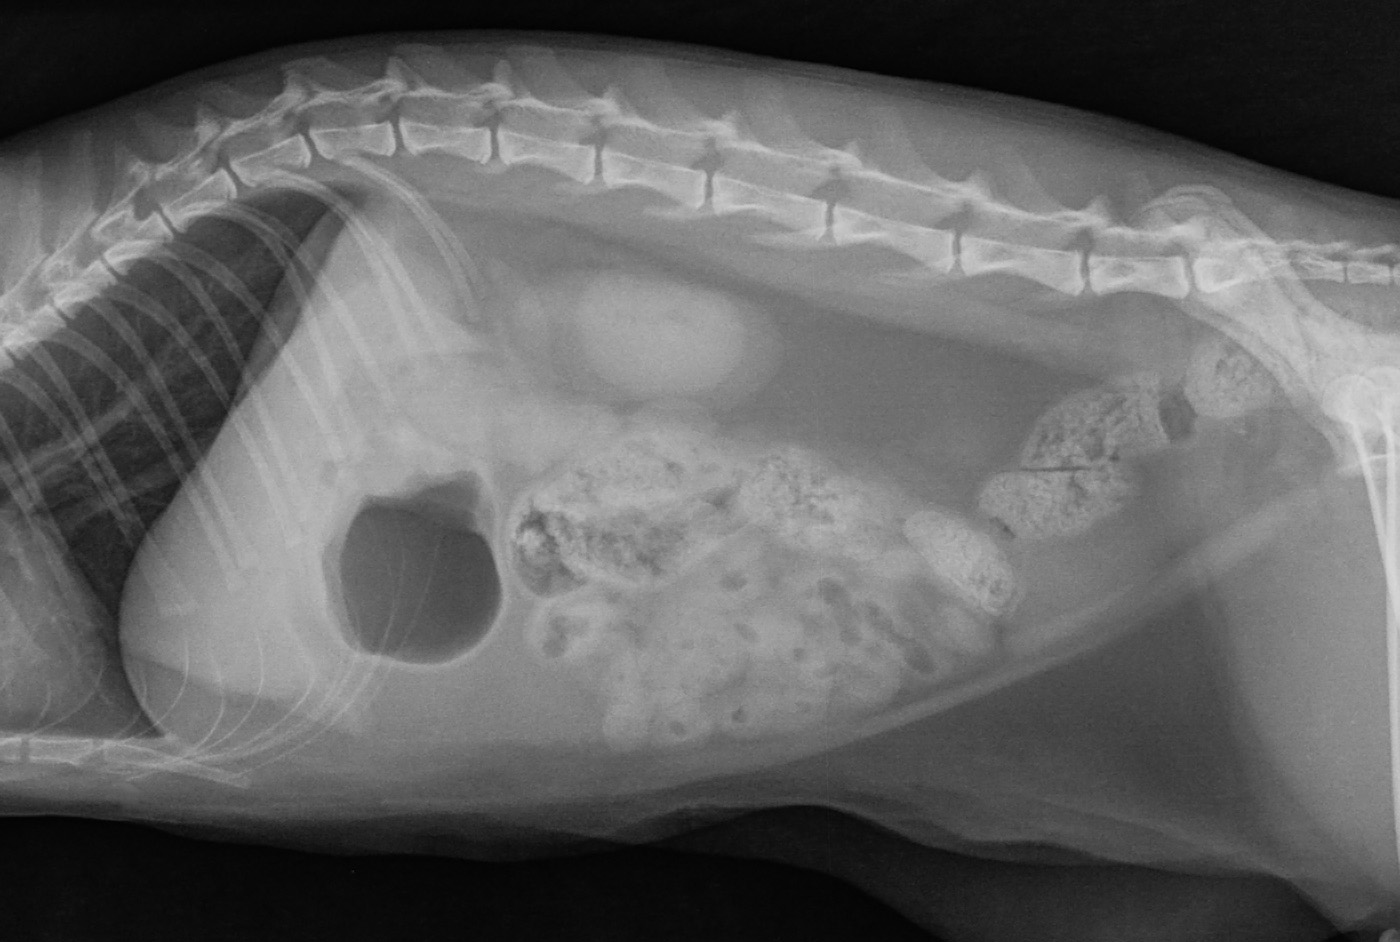

RadioQuiz 13 – Donnez-lui un petit sac

Signalement: chatte domestique stérilisée de 2 ans

Histoire clinique: vomissements aigus depuis 2 jours